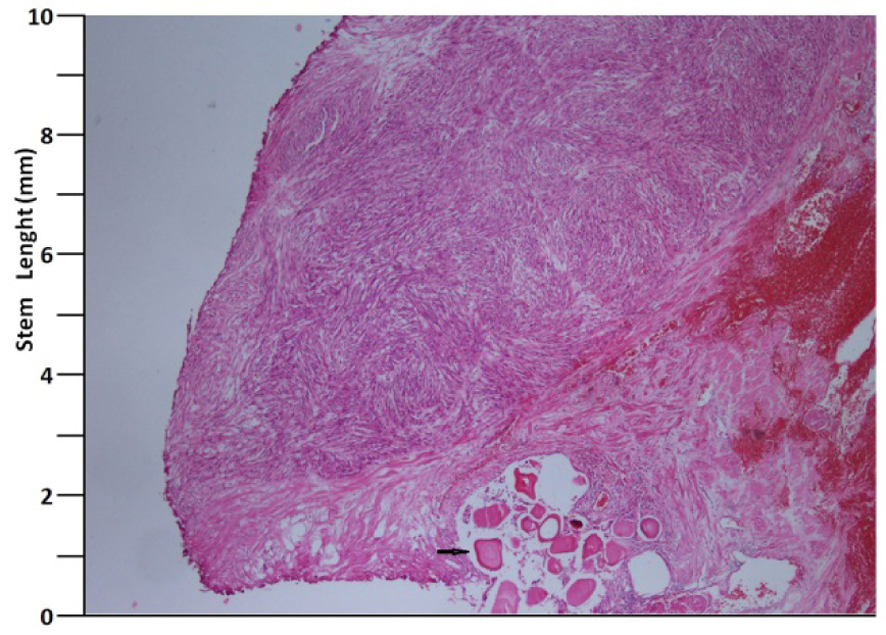

A 41 years old man presented with low urinary tract symptoms lasting for 8 months and progressing steadily. Percutaneous cystostomy catheter was inserted to the patient who could not be catheterized via transurethral route. His laboratory investigations were as follows: hepatic function tests and alkali phosphatase normal; urea: 51 mg/dL; creatinine: 1.48 mg/dL; complete urinary analysis: plenty of erythrocytes and 3 - 4 leukocytes per field; no growth in the urine culture. PSA was measured as 0.7 ng/mL. The prostate was palpated as diffusely hard in the digital rectal examination. The patient underwent palliative transurethral prostatic resection. On the endoscopic view, the crista urethralis, verru montanum and prostatic urethra had irregular anatomy and the prostatic urethra appeared to be obliterated due to presence of tumor. Macroscopically, 25 cc of tissue was resected. Pathologic examination revealed high-grade spindle cell sarcoma of the prostate and widespread mitosis and necrosis in 8 of 10 magnification fields (Fig. 1, 2). In immunohistochemical examination presence of actin, vimentin, desmin, CD34, S100 and PR was examined. Diagnosis of spindle cell leiomyosarcoma was made (Fig. 3). PET/BT scanning revealed widespread lung metastases. Adjuvant chemotherapy was scheduled.

![]() Click for large image | Figure 1. H&E, × 40 (arrow: corpora amilacea). |